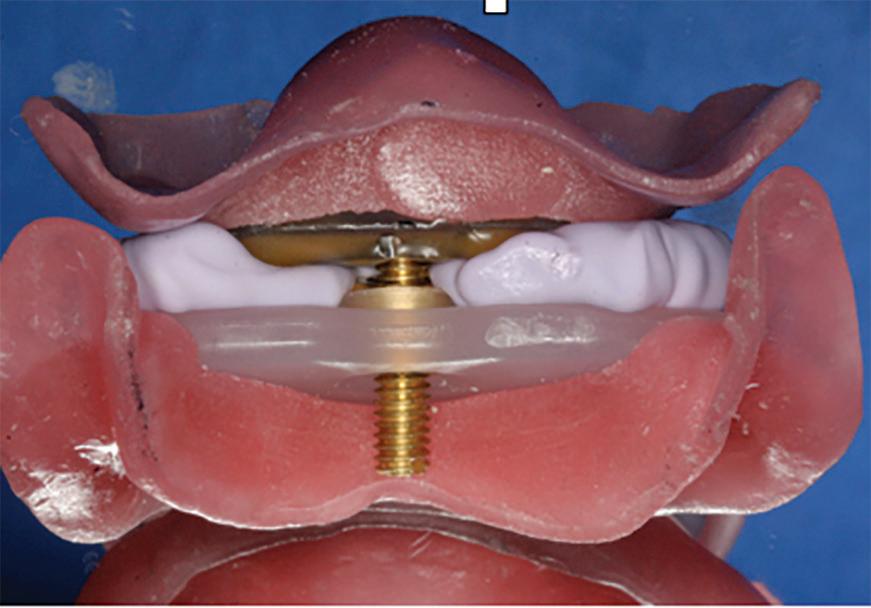

The gothic arch tracing technique has been found by many clinicians to produce the most accurate centric relation record, and it has the added benefit of being made at the correct vertical dimension of occlusion.4 The patient is fitted with a maxillary striking plate and a mandibular ball bearing pin (Massad Jaw Recorder, Global Dental Impressions Trays.) The correct vertical dimension of occlusion is determined with the maxillary plate and mandibular pin placed intraorally. When the patient closes so that the mandibular pin touches the maxillary plate and rubs the pin anteriorly and laterally (left and right), an arrow or gothic arch tracing is inscribed on the plate. The tip of this arrow represents the patient’s true centric relation (Fig 4). The maxillary striking plate and mandibular pin are then joined together at this arrow tip, producing an extremely accurate jaw relation record (Fig 5). The maxillary and mandibular casts are mounted on the articulator using this jaw relation record (Fig 6).